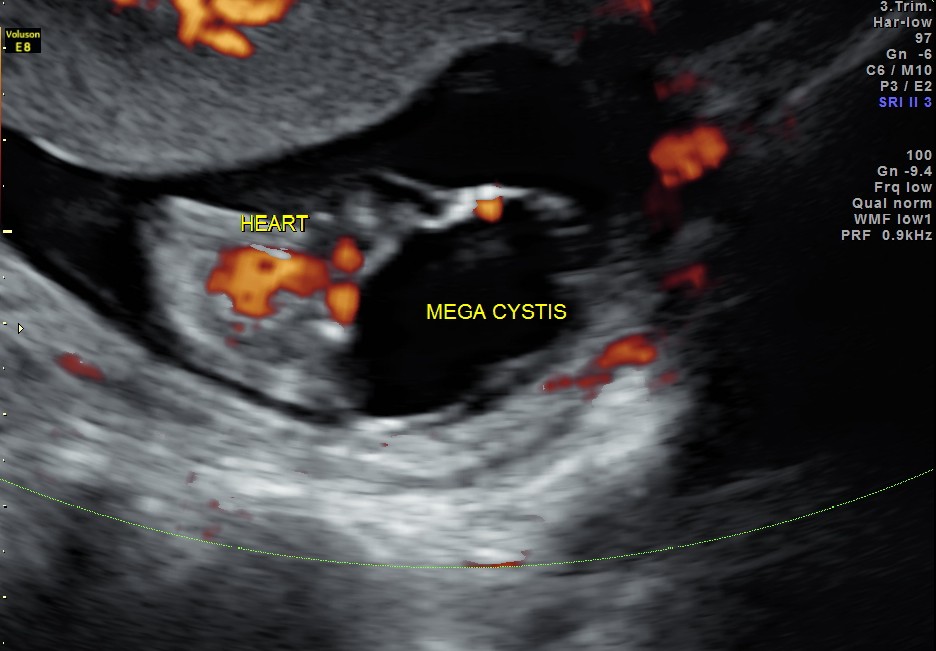

A large cystic mass was made out in the lower abdomen.

Will show an enlarged bladder

Ancilliary sonographic findings

- may show evidence of oligohydramnios

- may show associated renal anomalies